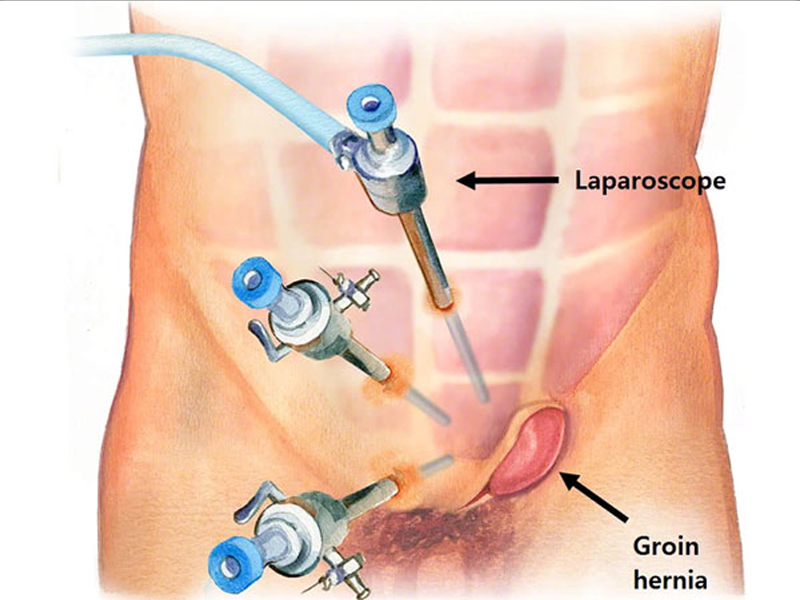

Laparoscopic Hernia Surgery

A hernia occurs when fatty tissue or an organ pushes through a weak place in the surrounding connective tissue...

Laparoscopic Surgery

The process takes its name from the laparoscope, a slender tool that has a tiny video camera and light on the end. When a surgeon inserts it through a...